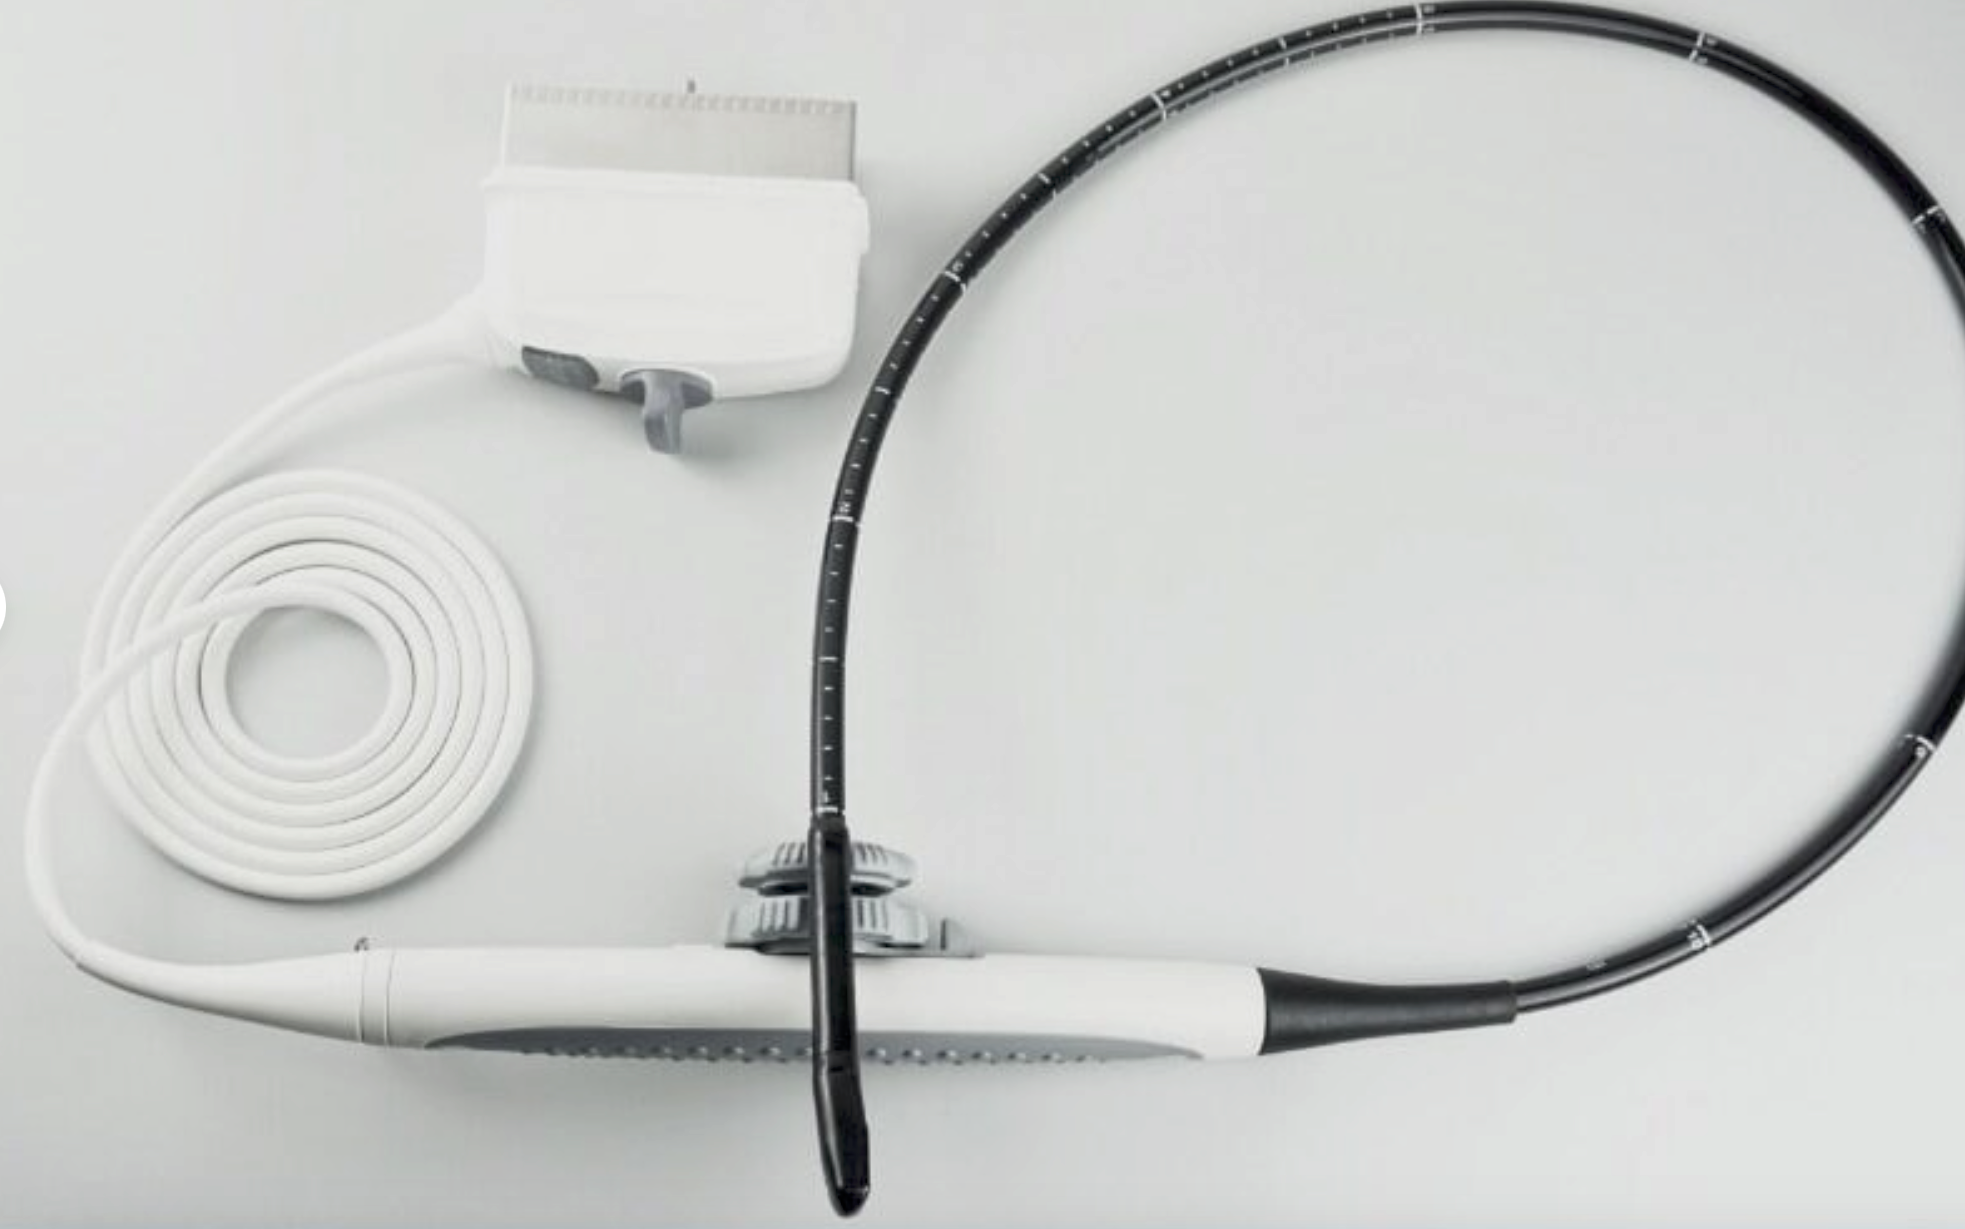

Samsung EC4-9/10ED Ultrasound Probe / Transducer

Sale price$ 10,545.18